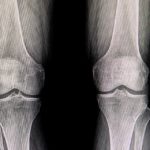

A glucosamina e a condroitina são substâncias, vendidas na forma de suplemento, muito usadas no tratamento de osteoartrite, osteoartrose ou artrose. Esses compostos estão presentes nas cartilagens, e participam da proteção das articulações.

Assim, o uso do suplemento pode ajudar a melhorar a qualidade da cartilagem e impedir a sua degeneração, aliviando assim os sintomas de algumas doenças articulares.